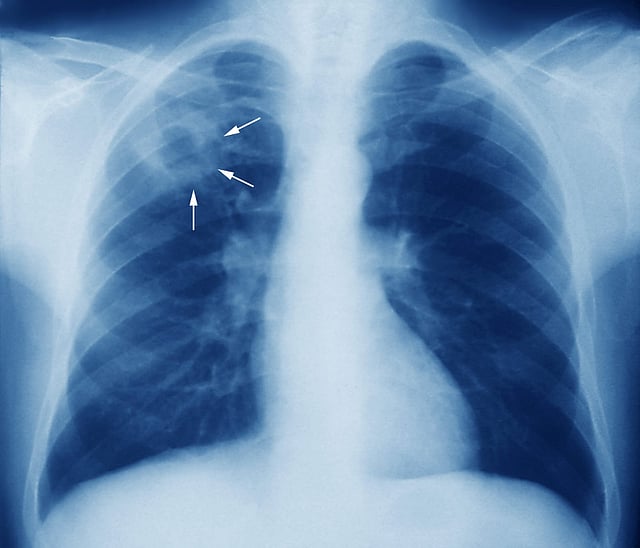

TB file photo